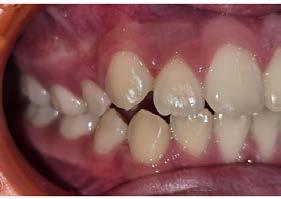

Paciente femenina de 9 años, manifestó: “No quiero hablar, ni me gusta mi sonrisa, porque me hacen burla”. En el interrogatorio a la mamá, se le realizó una historia clínica y consentimiento informado. Manifiesta ser respiradora bucal y roncar por las noches,

manteniendo el hábito de dedo hasta los 7 años, asmática de nacimiento y presenta alergias. A partir de los 8 años se diagnosticó con depresión y ansiedad. Para poder llegar a un diagnóstico y tratamiento adecuado, se le pide un estudio completo.

Se observó en la evaluación asimetría facial, tercio inferior aumentado, en la regla de quintos las líneas interpupilares no coinciden con la comisura labial, muestra 2/3 de las coronas superiores al sonreír y perfil retrusivo ocasionado por la distoclusión mandibular (Figura 1).

Su fonación no es clara, ya que presenta congestión nasal y hábito de lengua. Las fotografías intraorales de inicio se muestran en la Figura 2

Figura 2. Fotografias intraorales: A) fotografía de en oclusión, mordida abierta, línea media desviada. B) fotografía lateral, clase II subdivisión I.